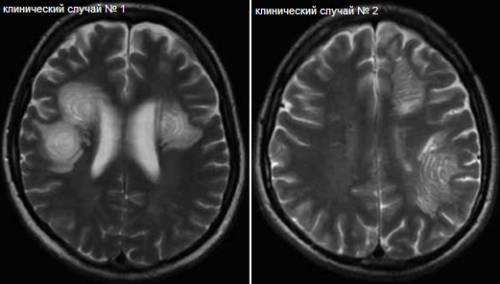

Концентрический склероз – это острая форма рассеянного склероза, которая характеризуется специфическим течением и отличается многослойным концентрическим строением демиелинизированных участков в головном мозге.

В белом веществе образуются участки разрушения миелина, которые приобретают форму колец и завитков.

По морфологическому строению демиелинезированные участки похожи на чередование зон без миелина и церебральной ткани с восстановленным или сохраненным миелином.

МРТ головного мозга позволяет определить наличие заболевания еще при жизни.